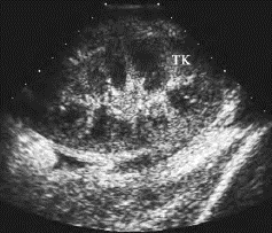

(1)肾脏肿大,锥体水肿,皮、髓质对比消失,分界不清(图29-14)。

图29-14 移植肾排异声像图

肾脏肿大,锥体水肿,皮、髓质对比消失,分界不清